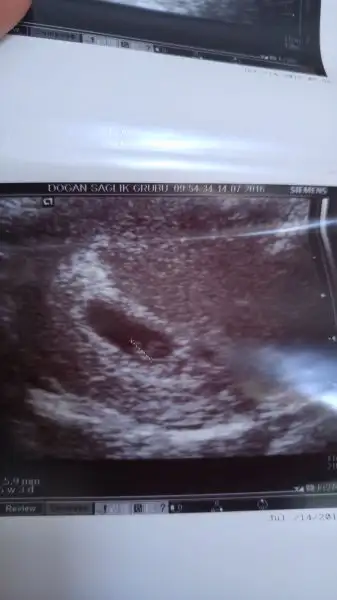

Havalianne__ canim zahmet olmazsa benim kesemi de yorumlar misin? 6+1 karindan